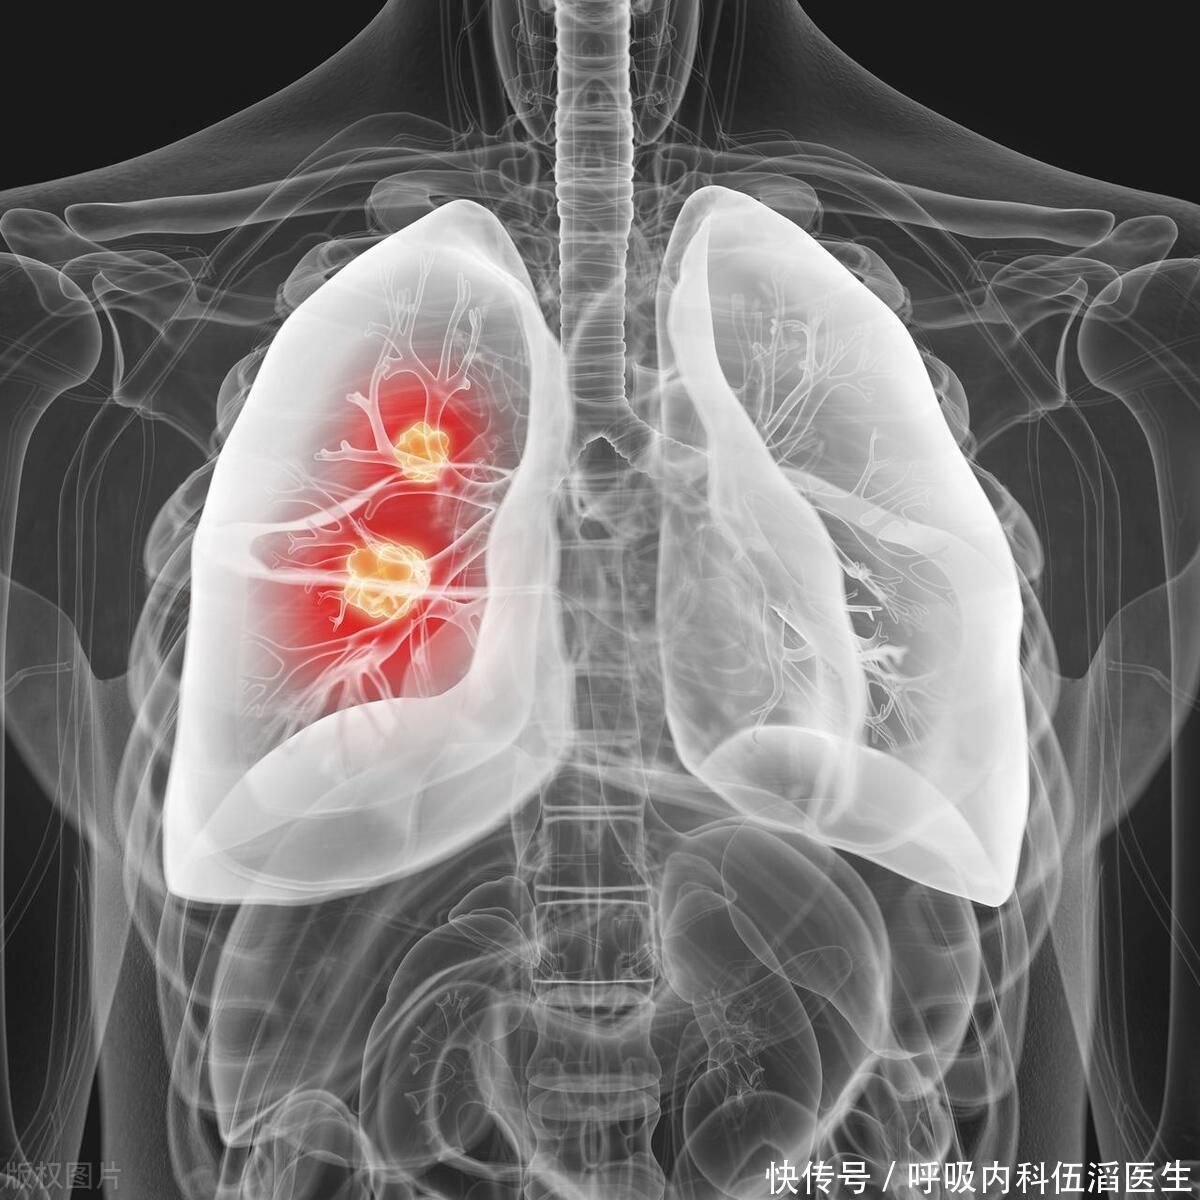

肺癌,作为全球最为常见的癌症之一,其高死亡率备受关注。其严峻形势迫切需要引起社会各界的高度重视和关注。肺癌往往在早期无明显症状,导致晚期诊断增加了治疗的挑战和风险。这强调了早期筛查的必要性,以便及早发现和治疗该疾病。然而,身体往往会通过各种迹象向我们发出健康警报,其中一些迹象甚至可能在不太显眼的地方出现,比如双腿。本文将探讨肺癌与双腿出现的三个可能迹象,以及为什么早期筛查对于提高生存率至关重要。

肺癌早期发现关系到治疗成功率和生存率,这一现实不容小觑,应引起社会广泛关注和高度重视。早期肺癌通常可以通过手术完全切除,而晚期肺癌的治疗选择则更加有限,通常涉及化疗、放疗或靶向治疗等方法。

早期筛查采用低剂量计算机断层扫描(LDCT),这种专为尽早发现肺癌而设计的影像学检查备受肯定,其精准度和有效性在专业领域获得了广泛认可。据已有证据表明,定期进行低剂量计算机断层扫描(LDCT)筛查已被证实对于长期吸烟等高风险人群可显著降低肺癌死亡率。